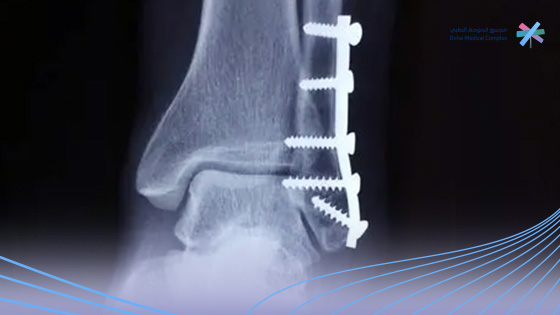

منذ أسبوعينتكلفة عملية إزالة الشرائح والمسامير في السعودية تعتبر من الأسئلة الشائعة لدى الكثير من المرضى الذين خضعوا لجراحة تثبيت كسور سابقًا باستخدام الشرائح والمسامير المعدنية.

فبعد التئام العظم بشكل كامل، قد يوصي الطبيب بإجراء عملية إزالة الشرائح والمسامير لتجنب أي حدوث أي مضاعفات مستقبلية أو شعور بعدم الراحة.

إزالة الشرائح والمسامير من الجسم، تتم من خلال فتح الجرح السابق أو جزء منه، وذلك للوصول إلى الأدوات المعدنية وإزالتها بعناية.